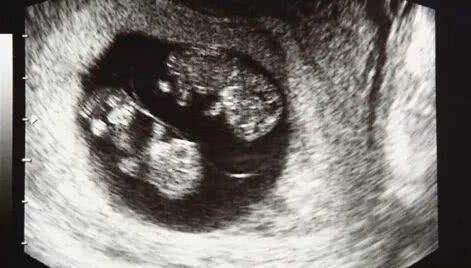

一段时间过后,在俩人身体态势差不多的时候又开始进入了备孕阶段,这一次两个人都很小心,第8周的时候去了医院做产检,这次的检查结果给小夫妻俩带来了惊喜,不仅怀孕,还是"双胞胎",一回家就迫不及待的把这个消息告诉了家人,开心的合不拢嘴。

但不幸的是又一次,到她怀孕第32周的时候,家人陪她来医院做检查,晴天霹雳一样的事情发生再次击垮了她,"又一次胎停了",这已经是她经历过的第三次胎停。况且这次怀的还是双胞胎,几乎接近崩溃边缘的她不敢相信,又做了一次彩超,但结果都是一样,确实是胎停了。家里人知道后伤心欲绝:"上辈子造了什么孽啊、真的要断子绝孙吗?"她听到更是难过了......